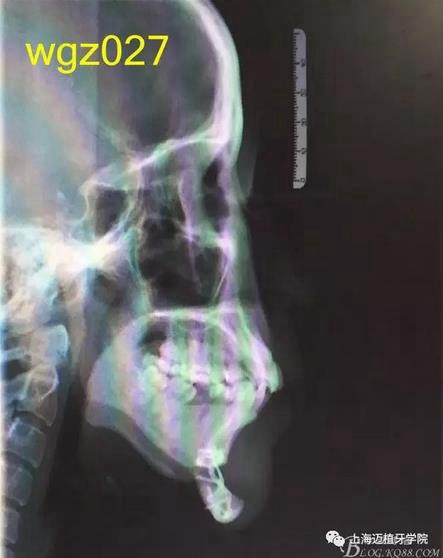

頭顱側(cè)位片:面型稍凸,上唇在E線前約1.5mm,下唇在 E前約1mm 。

SNA: 85↑ SNB: 75↓ ANB: 10↑ U1-L1: 113.6↓ U1-SN: 107.9

L1-M P: 88 ↓ Y軸角:65.8 FH-MP: 37↑ SN -M P: 45↑